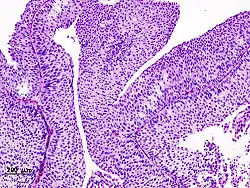

Histopathology of transitional carcinoma of the urinary bladder. Transurethral biopsy. Hematoxylin and eosin stain.

Transitional refers to the histological subtype of the cancerous cells as seen under a microscope.